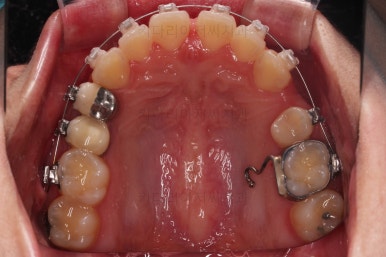

부산치아교정 이번 치료의 핵심인데요.

결손 부위에 미니스크류를 이용해서 뒤쪽 어금니들을 결손 부위로 앞으로 앞으로 계속 당겨줍니다.

얼굴모습에서의 중앙선도 지속저으로 체크하면서 한 쪽으로 치우침 없이 마무리를 해야 하고요.

틈새가 줄어들 때 까지 같은 작업을 반복합니다.

점점 틈새가 붙어가는게 보이죠?

계속 반복합니다.

틈새는 거의 다 붙어가는데 교합이나 중앙선 등을 위해 추가적으로 밀고 당기기를 해줍니다.

디테일을 좀 더 맞추고 부산치아교정 마무리를 합니다.

치아 갯수 및 사이즈 문제로 위아래의 정중선은 100% 일치시키긴 힘들지만 가능한 선에서 최대한 맞추었고요.

윗니가 1개 없는 상태에서의 교합도 잘 맞추고 마무리를 했습니다.

다시 틈새가 벌어지지 말라고 유지철사를 붙여주었고요.